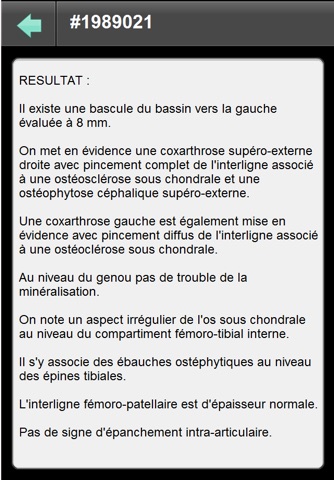

Cette application permet de consulter ses résultats dimagerie (images et compte rendu) en mettant en oeuvre une connexion sécurisée avec un serveur SYNAPSE Wave hébergé au sein la structure radiologique équipée, ayant réalisé lexamen radiologique.

Dans longlet Examen :

- Renseignez le numéro dexamen et le mot de passe associé pour accéder aux images de lexamen et à son compte-rendu